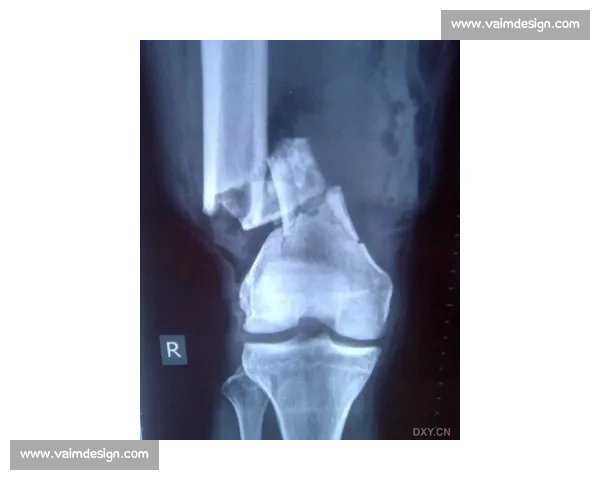

随着医学技术的不断进步,现代医疗手段在骨折治疗中的应用越来越广泛。例如,影像学技术如X光、CT扫描和MRI已经能够精准地定位骨折位置、评估骨折类型和监测恢复过程。通过这些影像学检查,医生可以及时了解骨折愈合情况,调整治疗方案。

此外,骨折固定技术的进步使得骨折治疗更加精确和有效。传统的石膏固定已逐渐被现代的外固定架、内固定钢板等方法取代,这些技术不仅能更好地固定骨折部位,还能减少患者的恢复时间,减少并发症的发生。